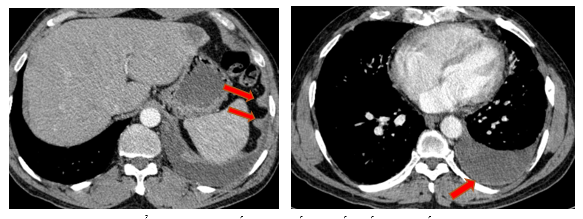

- Chụp cắt lớp vi tính lồng ngực (08/2025): Khối rốn phổi trái ôm quanh nhánh phế quản thùy dưới trái kích thước 28x26mm, dày tổn chức kẽ vách liên tiểu thùy và nhiều nốt đặc lan tỏa khắp nhu mô, đường kính <7mm. Màng phổi trái có vài nốt đặc ngấm thuốc nốt lớn nhất kích thước 17x15mm Khoang màng phổi trái có dịch dày 54mm. Nhiều hạch to trung thất, rốn phổi hai bên và hố thượng đòn có hoại tử trung tâm, hạch lớn nhất kích thước trục ngắn 22mm.

Hình 01: Nhiều hạch to trung thất, rốn phổi hai bên và hố thượng đòn có hoại tử trung tâm, hạch lớn nhất kích thước trục ngắn 22mm

- Chụp cắt lớp vi tính lồng ngực (11/2025): Màng phổi vùng rốn phổi trái dày, dày tổ chức kẽ vùng ngoại vi đáy phổi hai bên. Màng phổi trái có vài nốt đặc ngấm thuốc nốt lớn nhất kích thước 17x15mm. Khoang màng phổi hai bên không có dịch – khí (Tổn thương giảm đáng kể so với phim chụp 08/2025). Trung thất, rốn phổi hai bên, hố thượng đòn trái có vài hạch, hạch lớn nhất kích thước 12x6mm. Vài nốt đặc xương rải rác thân đốt sống, các cung xương sườn hai bên.

Hình 07: Hạch thượng đòn trái giảm đáng kể kích thước, từ 22mm còn 7mm sau điều trị

Hình 10: Không còn thấy tổn thương hạch trung thất nhóm 2 sau điều trị

- Khối u rốn phổi trái thoái triển gần hoàn toàn, các tổn thương dày tổ chức kẽ vách liên thùy và nốt đặc rải rác hai trường phổi phổi giảm rõ

- Không còn tràn dịch màng phổi.

- Hạch trung thất và thượng đòn: giảm kích thước rõ rệt, nhiều hạch không còn quan sát được trên phim chụp.